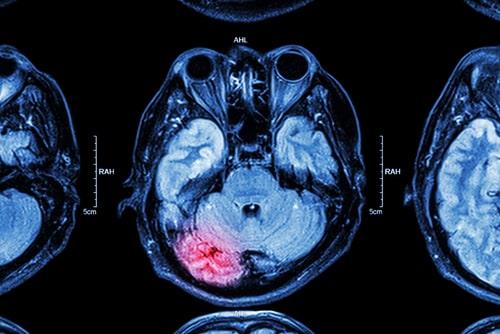

In recent years, there has been increasing awareness of the dangers that professional athletes face due to the high risk of serious brain injury. The risk is heightened if you play a sport with a higher chance of repeated trauma to the head, like in hockey, wrestling, and football for example. The repeated hits to the head suffered by someone who has been playing a particular sport professionally for several years can lead to the development of what is known as chronic traumatic encephalopathy (CTE), which can result in severe disability. If a loved one suffered brain trauma that developed into CTE, speak with a knowledgeable Naperville, IL personal injury attorney with experience in similar cases to understand how to move forward.

CTE is linked to repeated head trauma, and professional athletes are among the groups with the highest risk of developing it. This disease often gets worse over time and can even lead to dementia. There are four main stages of CTE, with the symptoms associated with these stages generally appearing between eight and ten years after the repetitive brain trauma. The stages are: